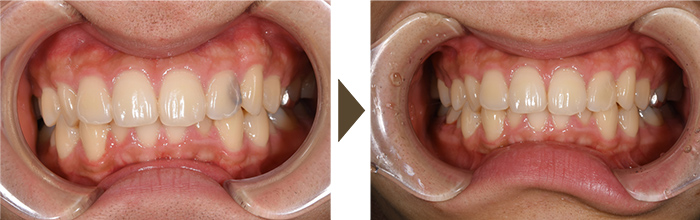

CAD/CAM(キャドカム)冠

むし歯になり、被せ物をしなければならない状況になった場合、通常奥歯に関して、保険診療では銀歯しか認められていませんでした。

ただ、保険診療でも最近、どの歯なら良いとルールは決められていますが(具体的には前から数えて4番目、5番目の歯)白い被せ物を入れることができるようになりました。

当院ではその治療にも対応しております。ただ、強度として、セラミックなどと比較すると、割れやすいなどの欠点もありますので、十分にご説明の上、最良の治療をご提案いたします。